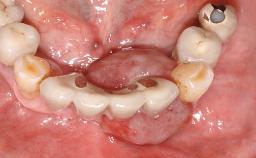

Early (Type 2) placement in a healthy, non-smoking male patient aged 28 years who required removal and replacement of the maxillary right central incisor due to external root resorption. A horizontal bone deficit requires a simultaneous augmentation procedure. The overall esthetic risk is high due to the horizontal bone deficit, medium to high lip line with exposure of the soft tissue margin when smiling, and the patient’s high esthetic expectations.

After flapless tooth extraction and a healing period of 6 weeks, a standard-diameter one-piece implant is placed. A gap between the implant and the facial bone wall is filled with autogenous bone chips harvested from the anterior nasal spine and covered with DBBM particles. Contour augmentation on the facial aspect is achieved using DBBM particles and a collagen membrane, according to the principles of guided bone regeneration (GBR). The flap is coronally repositioned for semisubmerged healing.